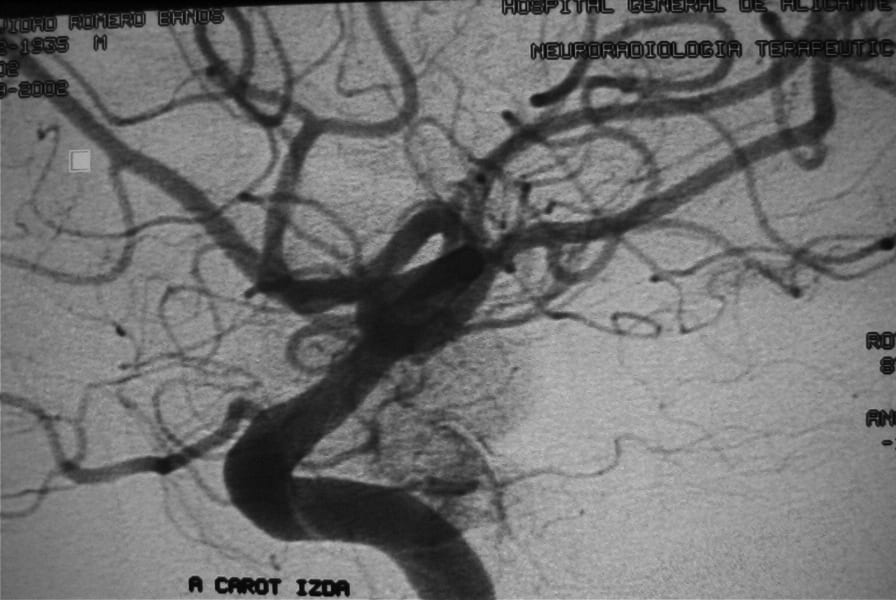

El diagnóstico se puede confirmar y el tumor localizar mediante:

• Angiografía cerebral